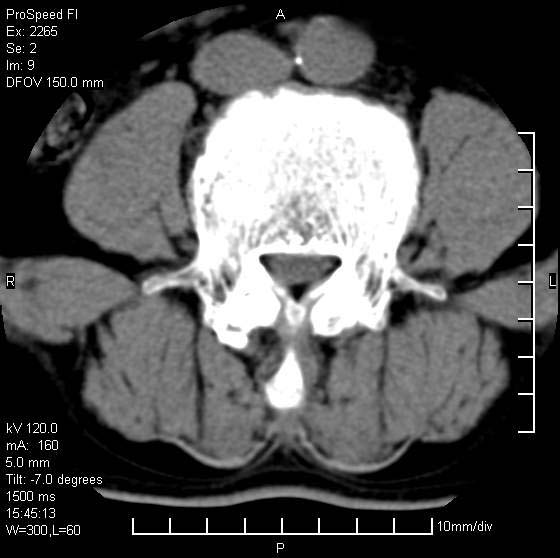

以下是引用qiushi在2007-8-22 17:26:00的发言:[br]没骨窗![br] 1、 l5~s1间盘膨出伴轻度突出(中央型)、变性。[br] 2、l4~5间盘膨出伴突出(右侧远外侧型)。[br] 3、l3~4间盘膨出。[br] 4、腰椎退行性变。[br]

以下是引用随缘的人在2007-8-22 20:56:00的发言:[br]腰椎退行性变:1。l4/5,l5/s1膨出[br] 2。l5/s1间盘退行性变 [br] 3。腰椎骨质增生

以下是引用liaizhi在2007-8-22 22:13:00的发言:[br]1,l4-5锥间盘膨出,2,l5-s1椎间盘膨出并退变(椎间盘呈真空征);3,血管瘤(椎体骨小梁稀疏粗大)?